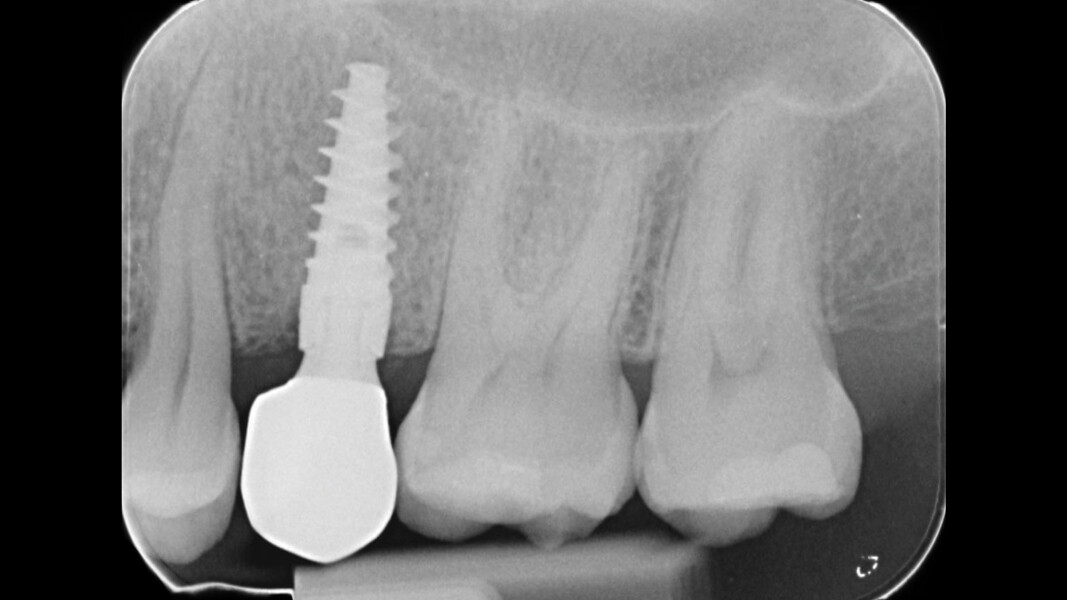

Una paziente di 50 anni presentava un premolare superiore non recuperabile. Dopo CBCT preoperatoria (T0) (Fig. 1), si è proceduto all’estrazione atraumatica e alla gestione dell’alveolo mediante posizionamento vestibolare di una membrana corticale eterologa (Lamina fine 0,7 mm, 35 × 15 mm, OsteoBiol) e riempimento con spugne di collagene (Figg. 2, 3). Sono stati applicati punti di sutura in nylon non riassorbibile 4/0. Dopo sei mesi di guarigione, una nuova CBCT (T1) ha consentito la valutazione della qualità ossea. Per la fase implantare è stato eseguito un lembo secondo la tecnica del roll flap, con preservazione delle papille interdentali e aumento del tessuto cheratinizzato (Fig. 4). È stato inserito un impianto JD Evolution Plus (4,3 × 11,5 mm) ottenendo un’eccellente stabilità primaria. Durante la chirurgia è stato prelevato un campione osseo per analisi istologica (Fig. 5).  Il lembo è stato suturato con nylon 4/0 intorno all’abutment di guarigione. Dopo due mesi, la paziente è stata riabilitata con una corona monolitica in zirconia realizzata da impronta digitale intraorale (Fig. 6).

L’analisi CBCT ha evidenziato un mantenimento del volume osseo con valori comparabili tra T0 e T1.

• T0: larghezza 9,22 mm, altezza 17,12 mm;

• T1: larghezza 9,46 mm, altezza 17,02 mm.

L’esame istologico ha confermato la presenza di osso neoformato mineralizzato con buona integrazione del materiale eterologo residuo. L’inserimento implantare è risultato stabile e privo di complicanze (Figg. 7-12).